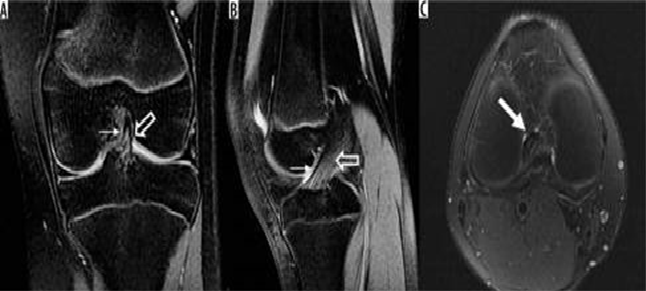

Hình 9. Rách sụn chêm và mô hạt đang lành sau mổ. A là hình ảnh T1 xóa mỡ sau khi tiêm thuốc tương phản trong khớp với tín hiệu tuyến tính sụn chêm bên có giá trị trung gian về cường độ tín hiệu (mũi tên trắng), so với chất tương phản sáng được tiêm vào không gian khớp (mũi tên mở), có thể đại diện cho mô hạt trong sụn chêm bên đã được phẫu thuật sửa chữa trước đó. B là hình ảnh T1 xóa mỡ sau khi tiêm thuốc tương phản nội khớp cho thấy khiếm khuyết cường độ sáng tương phản (mũi tên đen) ở sụn chêm giữa, biểu thị vết rách xuyên tâm.

Hình 14. Dây chằng chéo sau: rách một phần và thoái hóa niêm mạc. A là hình ảnh pd xoá mỡ sagital với tín hiệu tăng lên ở phần giữa của dây chằng chéo sau thể hiện vết rách một phần trước đó (mũi tên). B là hình ảnh pd xoã mỡ cho thấy sự xuất hiện "đường ray xe điện" (mũi tên) của dây chằng chéo sau phù hợp với thoái hóa niêm mạc

Hình 15. Đứt dây chằng chéo sau. Hình ảnh pd xoá mỡ sagittal cho thấy dây chằng chéo sau bị đẩy hoàn toàn từ sự chèn ép của nó (mũi tên).